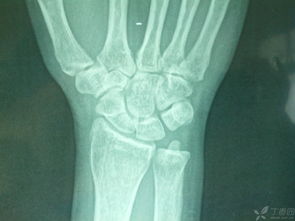

看了你追加描述和圖片,基本確定是骨折!不打算去醫(yī)院的話就按照我上面說的做,狠狠心找到骨折的地方,試著做一下整復(fù),外邊用硬紙殼固定!可以去買一些人藥!狗狗會很快好起來的

根據(jù)外傷史和局部癥狀可以確診,必要時對寵物寶貝進(jìn)行X射線檢查或照相。